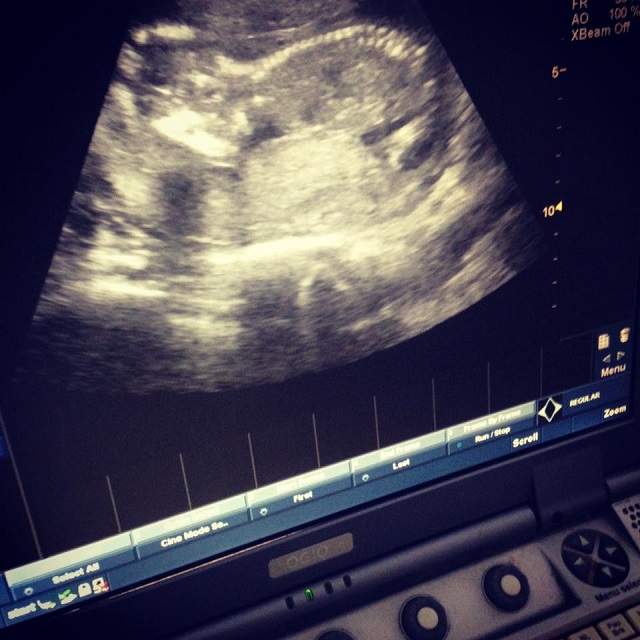

FOTO / Emoții de nedescris! Un fost concurent la "Mireasă pentru fiul meu" și-a văzut copilul la ecografia din trimestrul 1!

| Galerie Foto | Imaginea 1 din 3